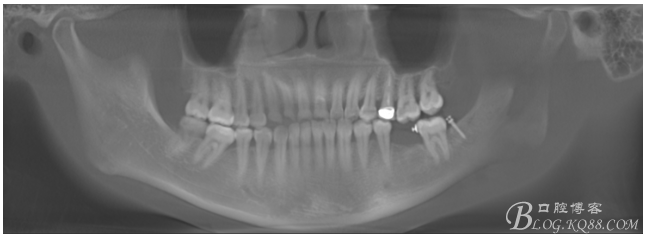

檢查:36.46缺失,36缺牙區(qū)近遠(yuǎn)中間隙約3mm,46缺牙區(qū)間隙約0.5mm,37.47.48近中傾斜,48近中面齲壞達(dá)牙本質(zhì)淺層,37牙周探診4mm,47近中探診深度5-6mm,不松,口內(nèi)照片及CT片如下:

術(shù)前CT